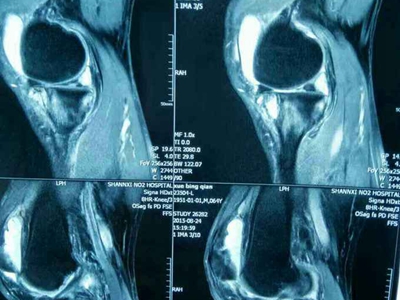

膝关节创伤性滑膜炎是指膝关节外伤后发生的膝关节滑膜无菌性炎症反应,急性损伤性膝关节滑膜炎,可发生于任何年龄。本病以关节疼痛、肿胀为主要临床表现。

膝关节创伤性滑膜炎可表现为局部胀痛,在膝关节完全伸直或属曲时胀痛感更明显,此外,由于局部淤血,可导致局部出现青紫色。局部可逐渐出现关节肿胀,并伴有活动受限、压痛等症状。